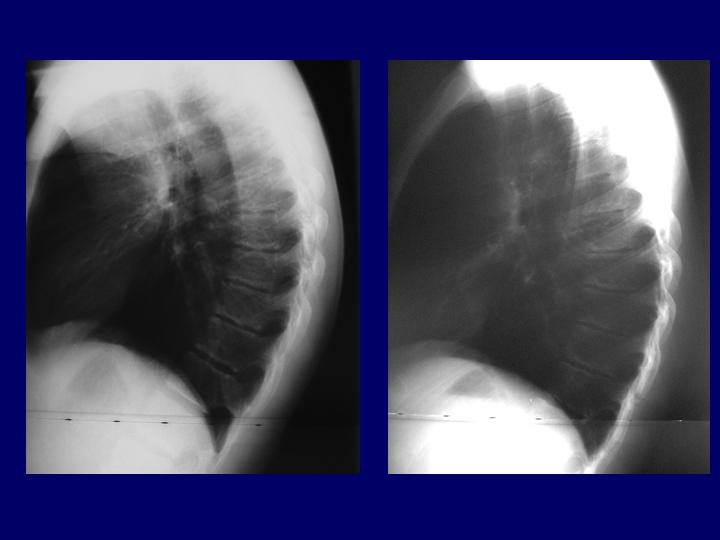

Hernias Discales